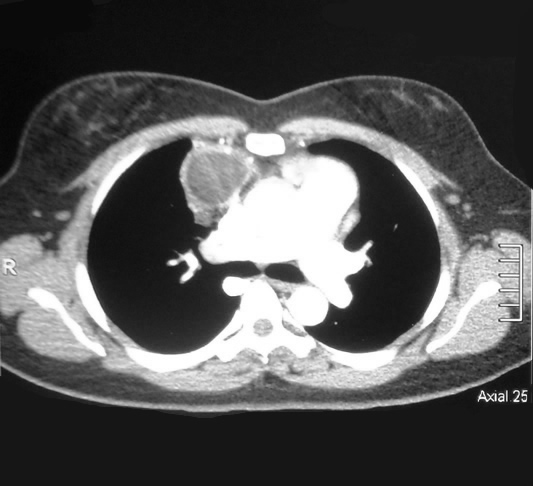

Tomografía del Tórax con Contraste

tomografia Corte axial 25

tomografia Corte axial 30

Corte Axial nivel carina bronquial

Corte Mediastinal a la altura de la carina.

Lesión redondeada por delante de aorta ascendente de aspecto homogéneo bien limitada, su cápsula es brillante y bien vascularizada.

Corte Axial nivel hileo pulmonar

Corte Mediastinal a nivel hileo pulmonar.

Lesión redondeada por delante de la aorta y a su derecha la vena pulmonar. contacta con la pared torácica anterior si alterarla.